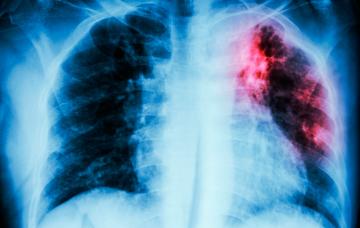

Qué es la sarcoidosis

La sarcoidosis es una enfermedad en la que se forman granulomas (cuerpos duros compuestos de una amalgama de células) en diferentes órganos, como el pulmón.

Diagnóstico de sarcoidosis

El diagnóstico de la sarcoidosis pulmonar se basa en pruebas de imagen, y es necesario que el médico descarte otras patologías antes de confirmarlo.